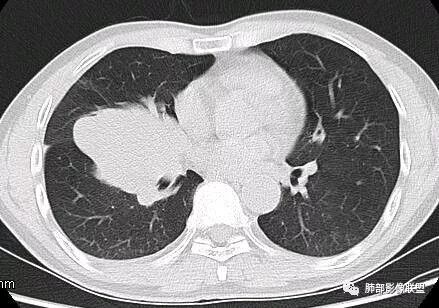

南边:深分叶、大肿块

南边:主体在下叶前基底段

南边:边缘膨隆

南边:中叶、下叶背段支气管推移

南边:中叶支气管腔内似有粘液栓,外侧段有炎性病变